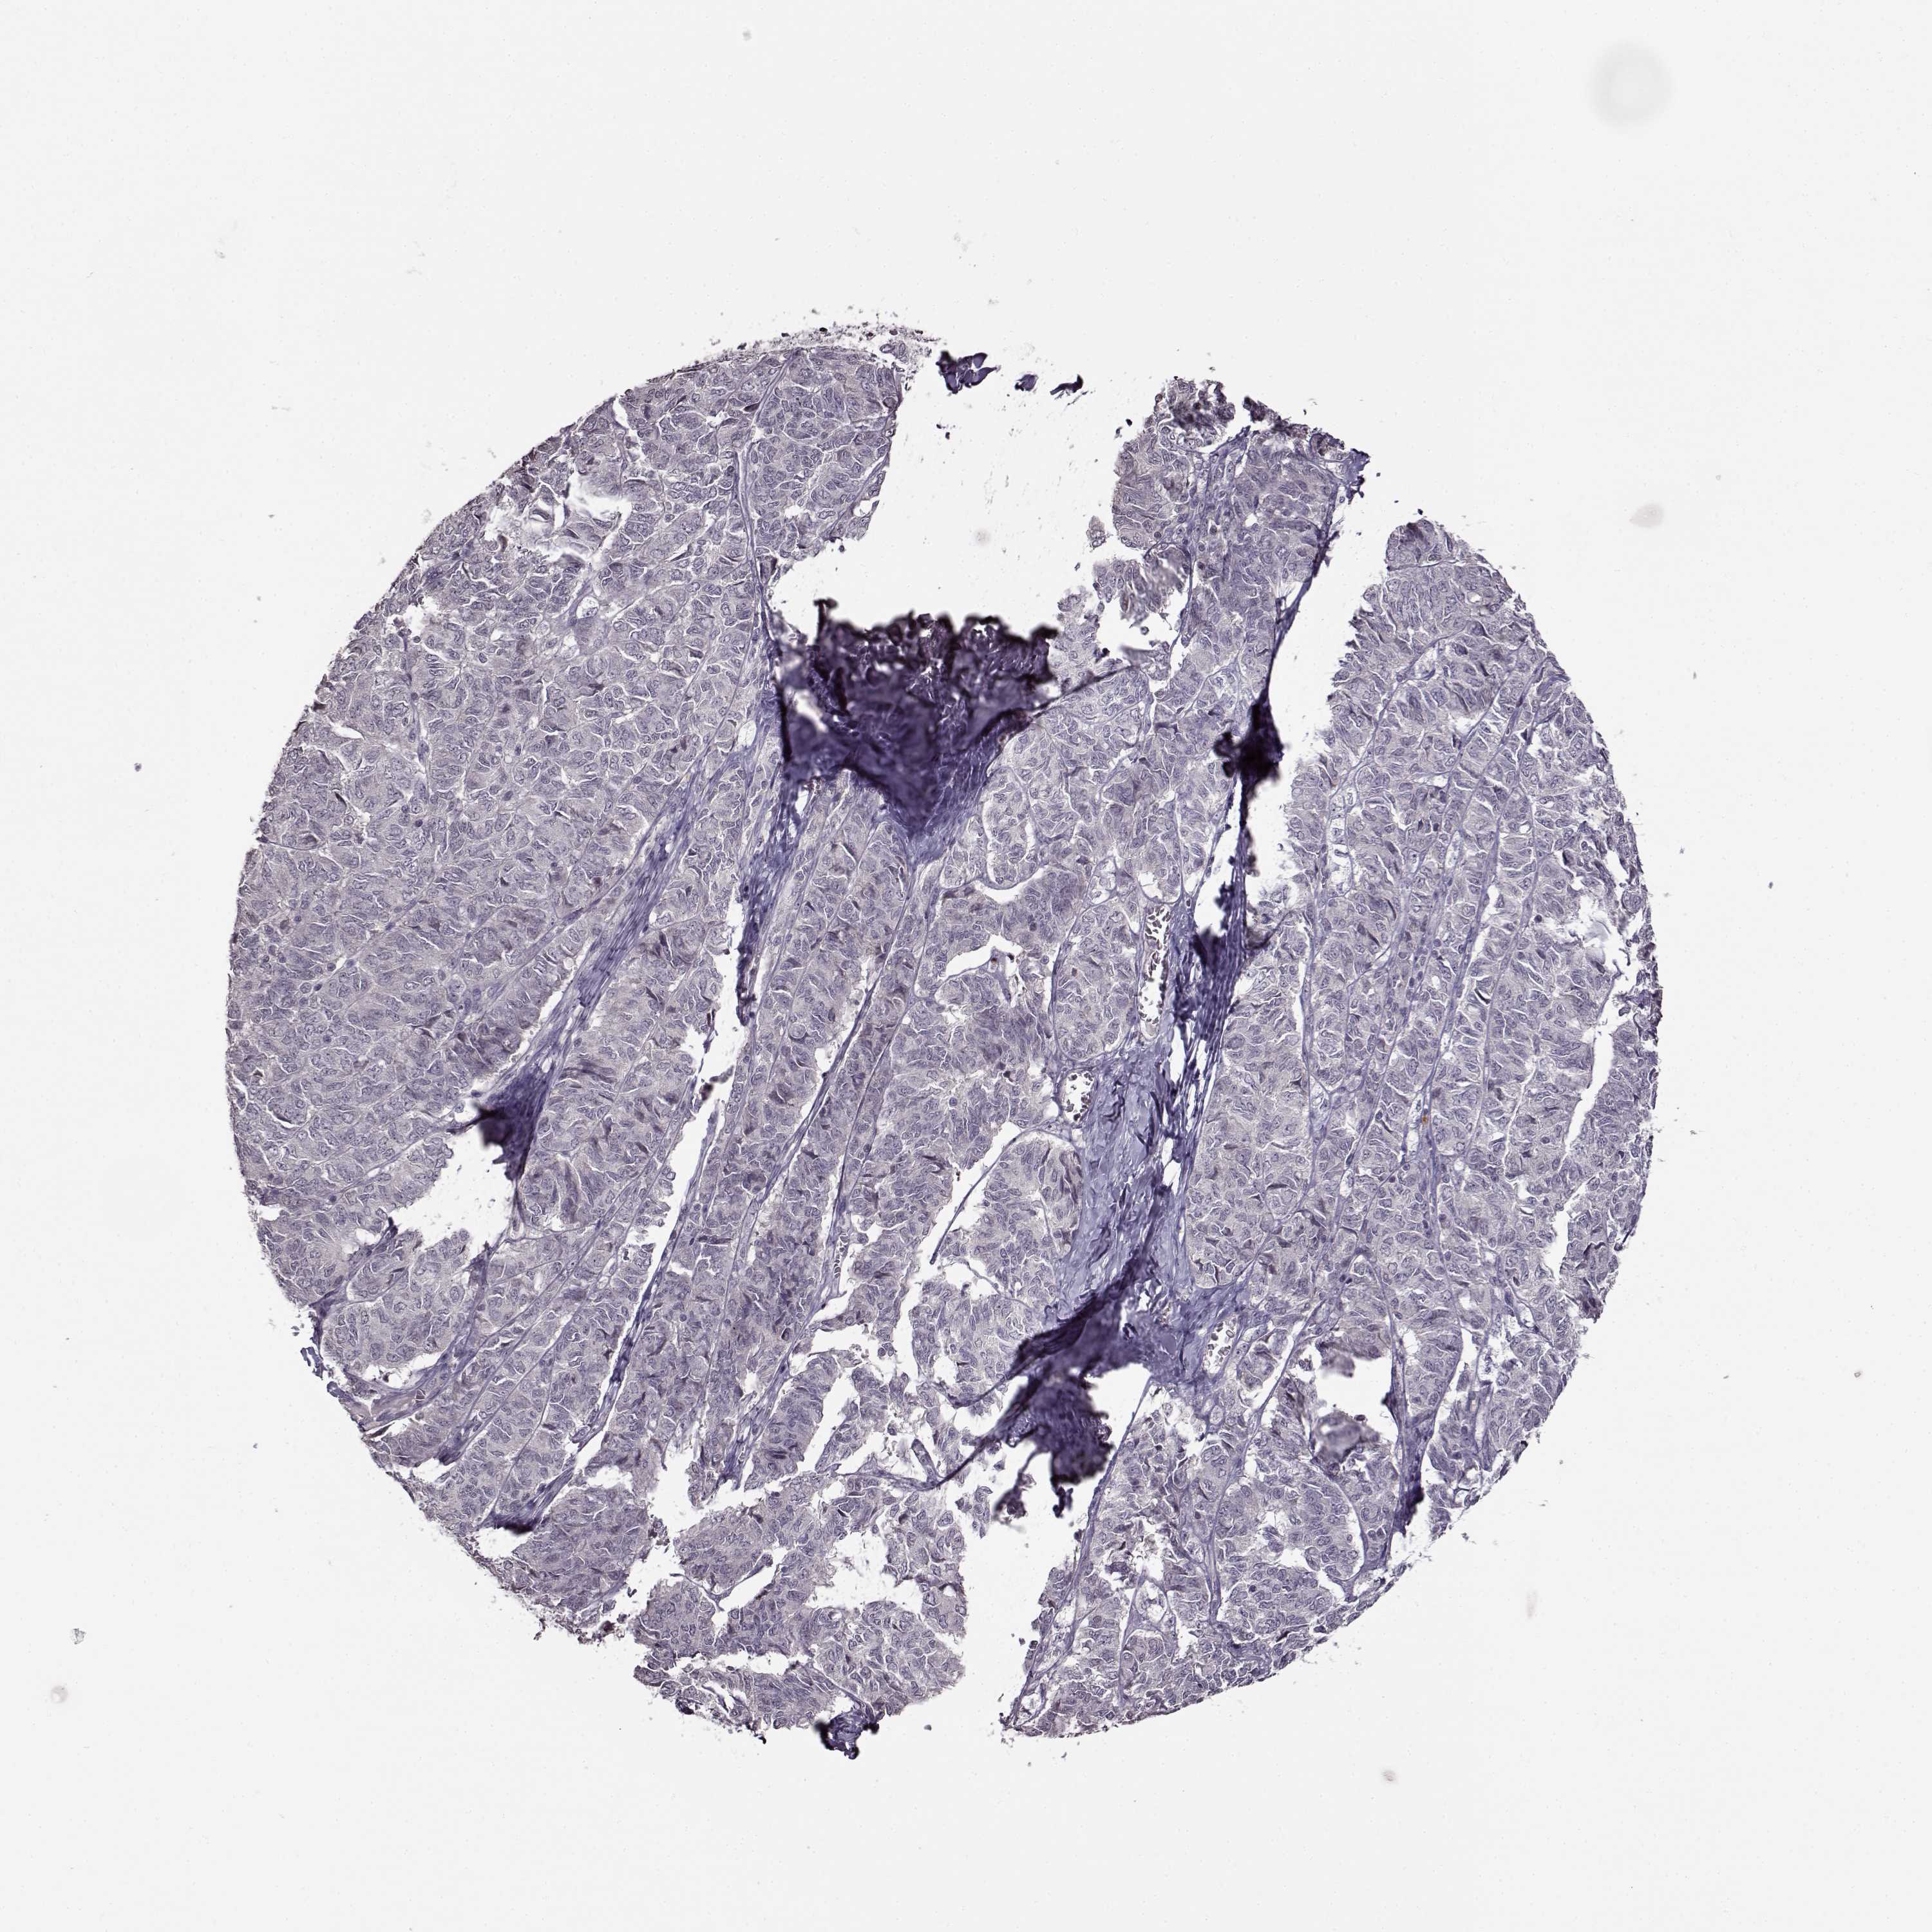

OVARIAN CANCER - Protein expressioni

A mouse-over function shows sample information and annotation data. Click on an image to view it in a full screen mode. Samples can be filtered based on level of antibody staining by selecting one or several of the following categories: high, medium, low and not detected. The assay and annotation is described here.

Note that samples used for immunohistochemistry by the Human Protein Atlas do not correspond to samples in the TCGA dataset.

Antibody stainingi

Antibody staining in the annotated cell types in the current human tissue is reported as not detected, low, medium, or high, based on conventional immunohistochemistry profiling in selected tissues. This score is based on the combination of the staining intensity and fraction of stained cells.

Each image is clickable and will lead to virtual microscopy that enables deeper exploration of all samples and also displays staining intensity scores, fraction scores and subcellular localization as well as patient and tissue information for each sample.

Antibody HPA069703

Antibody CAB023410

Staining

High

Medium

Low

Not detected

Intensity

Strong

Moderate

Weak

Negative

Quantity

>75%

75%-25%

<25%

None

Location

Nuclear

Cytoplasmic/membranous

Cytoplasmic/membranous,nuclear

Cystadenocarcinoma, serous, NOS

Cystadenocarcinoma, mucinous, NOS

Carcinoma, endometroid